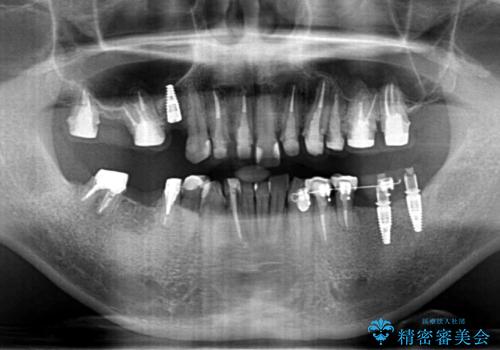

- 「少しずつ色々な箇所が悪くなり、歯医者に通い続けている。全ての歯を長持ちするような状態にできるような治療を受けたい。」、と全顎・総合的な治療を希望され来院されました。

根管治療・矯正治療・歯周外科・セラミック補綴を含む様々な治療オプションを駆使し、長期間良好な状態に保てるような治療計画を立案します。

矯正治療を絡めた総合的な治療をお行なったことで、理想的な咬合関係を確立し安定した噛み合わせで仕上げることができました。

また歯周外科を行うことで歯ぐきの腫れを改善し、清掃性を高めています。